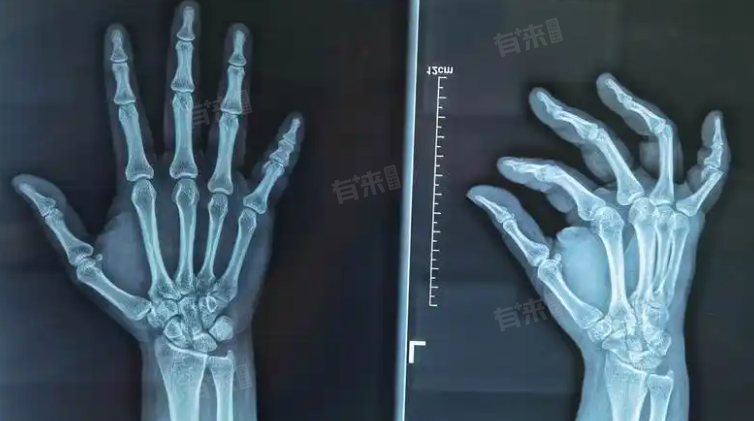

小手指骨折石膏固定治疗拆除石膏时间通常在3-8周甚至更长时间,因小指骨折程度、类型等诸多因素不同故每个患者的拆除时间不同。

- 小手指骨折是单纯的线性骨折,骨折断端对位良好,没有明显的移位和粉碎情况,在上述常规时间范围内就能达到较好的愈合,可以拆除石膏,骨折较为复杂,如粉碎性骨折、骨折断端有明显的移位且经过了复杂的复位操作,或合并有软组织严重损伤等情况,骨折愈合的时间会延长,石膏拆除的时间可能需要6周,甚至更久。

- 儿童的骨骼生长和愈合速度相对较快,对于小手指骨折,如果骨折情况不太复杂,通常在3-4周可以拆除石膏。这是因为儿童处于生长发育阶段,成骨细胞活跃,骨折愈合的时间相对成人较短。一般情况下,成人小手指骨折后石膏固定大约需要4-6周的时间拆除。成人骨骼的生长和修复能力不如儿童,需要相对更长的时间来完成骨折断端的愈合。

- 老年人由于身体机能衰退,骨骼中的矿物质含量减少,骨密度降低,骨折愈合速度明显减慢,小手指骨折后石膏固定可能需要 6-8周,甚至更长时间才能拆除。